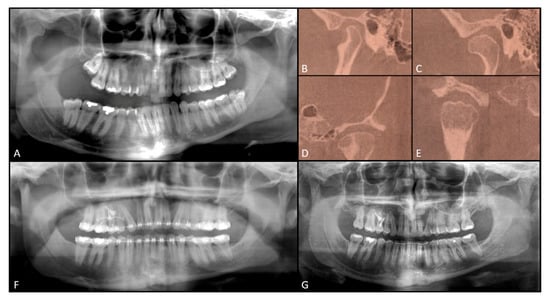

- Decompensating orthodontic treatment

2.1. First Step

2.2. Second Step

2.3. Third Step